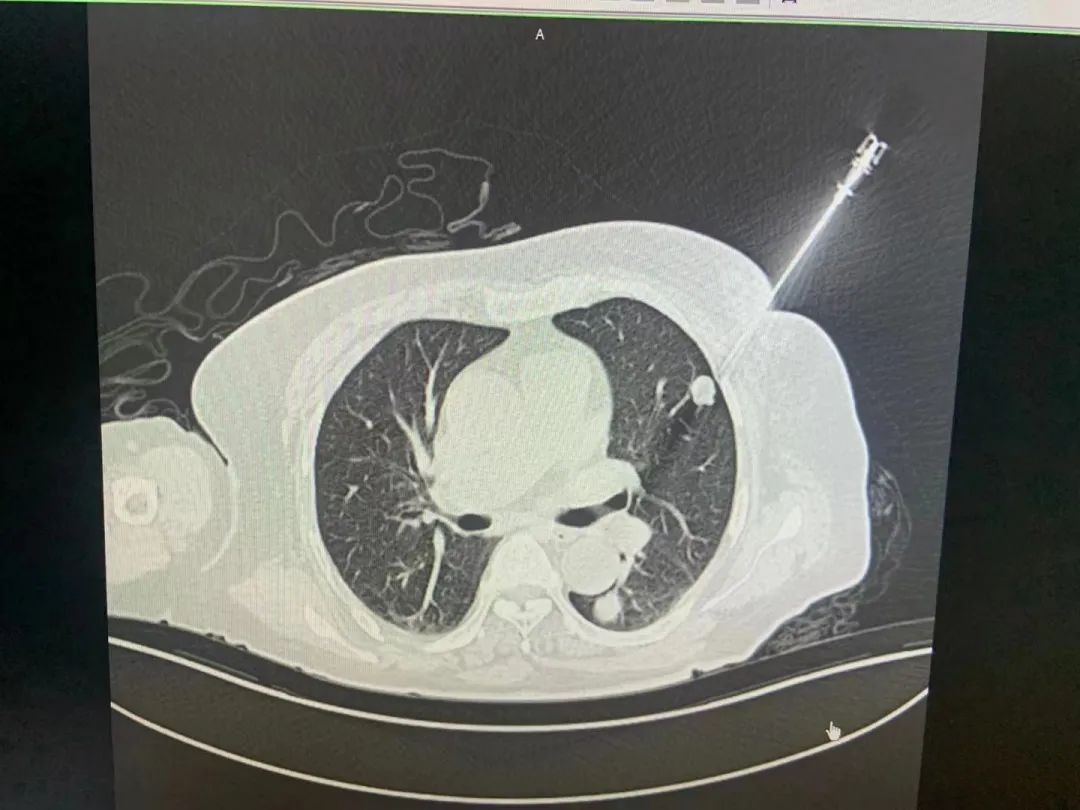

腫瘤穿刺機(jī)器人是睿觸科技成立后生產(chǎn)的第一款產(chǎn)品,如今已經(jīng)在長(zhǎng)三角兩家專(zhuān)科三甲醫(yī)院開(kāi)展臨床試驗(yàn)。這款手術(shù)機(jī)器人不僅將穿刺活檢精度提高了十倍以上,而且將穿刺時(shí)間縮短了數(shù)十倍,極大提高了手術(shù)效率和便捷度,降低了病人的痛苦。

“人體的腫瘤藏在很深的組織里,必須通過(guò)醫(yī)學(xué)影像,也就是CT等技術(shù)來(lái)查找?!眲忉尩溃凑諅鹘y(tǒng)的操作方法,腫瘤穿刺中手術(shù)機(jī)器人必須借助醫(yī)學(xué)影像來(lái)進(jìn)行引導(dǎo),然而這兩者之間其實(shí)是“互相不認(rèn)識(shí)的”關(guān)系?!耙?yàn)镃T和機(jī)器人是各自獨(dú)立的兩套坐標(biāo)系,必須借助光學(xué)傳感器來(lái)建立聯(lián)系,但這樣也會(huì)導(dǎo)致精度的損失,成像效果不理想,影響手術(shù)進(jìn)程?!币虼?,睿觸科技將這兩者進(jìn)行了大膽結(jié)合,用劉劍的話(huà)說(shuō),就是“讓他們互相認(rèn)識(shí)對(duì)方”。

“我們采取了全新的設(shè)計(jì),把人體的三維腫瘤信息實(shí)時(shí)地告訴機(jī)器人,讓機(jī)器人開(kāi)啟智慧之眼,比如距離有多遠(yuǎn)、角度差了多少度等等,這樣就能引導(dǎo)醫(yī)生來(lái)做更精準(zhǔn)的腫瘤治療手術(shù)?!比绱?,在腫瘤早篩領(lǐng)域,這樣一款精確、快速、安全的經(jīng)皮穿刺手術(shù)機(jī)器人,能讓更多腫瘤患者可以早發(fā)現(xiàn)、早診斷、早治療。